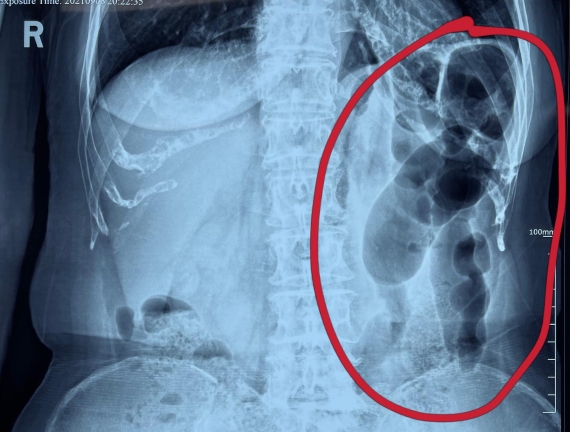

據(jù)省醫(yī)院消化病院消化二科姜子曄醫(yī)生介紹,韓大娘今年已經(jīng)73歲,家住哈爾濱市,一周前開始腹脹腹痛,有較為明顯的左側(cè)腹部疼痛,疼痛劇烈時會出現(xiàn)左側(cè)腹部鼓包情況,排氣排便后有所好轉(zhuǎn)。韓大娘家人見狀將其送到了黑龍江省醫(yī)院,門診檢查腹部平片提示為左側(cè)腹部積氣,口服全消化動力藥及通便治療后腹痛腹脹有所緩解,入院前再次突發(fā)左側(cè)腹痛加重伴有明顯腹脹,急診隨后以“腹痛腹脹原因待查”將韓大娘收入到消化病院消化二科。

姜子曄醫(yī)生熱情接待了韓大娘,為其進行了仔細查體,除了左側(cè)腹部壓痛并未見明顯異常,對癥給予灌腸后,韓大娘的腹脹有所緩解,第二天姜子曄醫(yī)生為韓女士進行了胃腸鏡檢查,也未見明顯異常。但此時韓大娘腹部平片結(jié)腸腸管擴張仍然很嚴重,腹痛腹痛也沒緩解,到底什么原因呢?消化二科主任陸以霞在查房時建議繼續(xù)給予韓大娘口服全消化動力藥,必要時灌腸治療,同時陸以霞主任在追問病史查體時發(fā)現(xiàn)韓大娘左下腹紅色皮疹和小水泡,反復抓撓腹部皮膚部分已結(jié)痂,高度懷疑為帶狀皰疹。